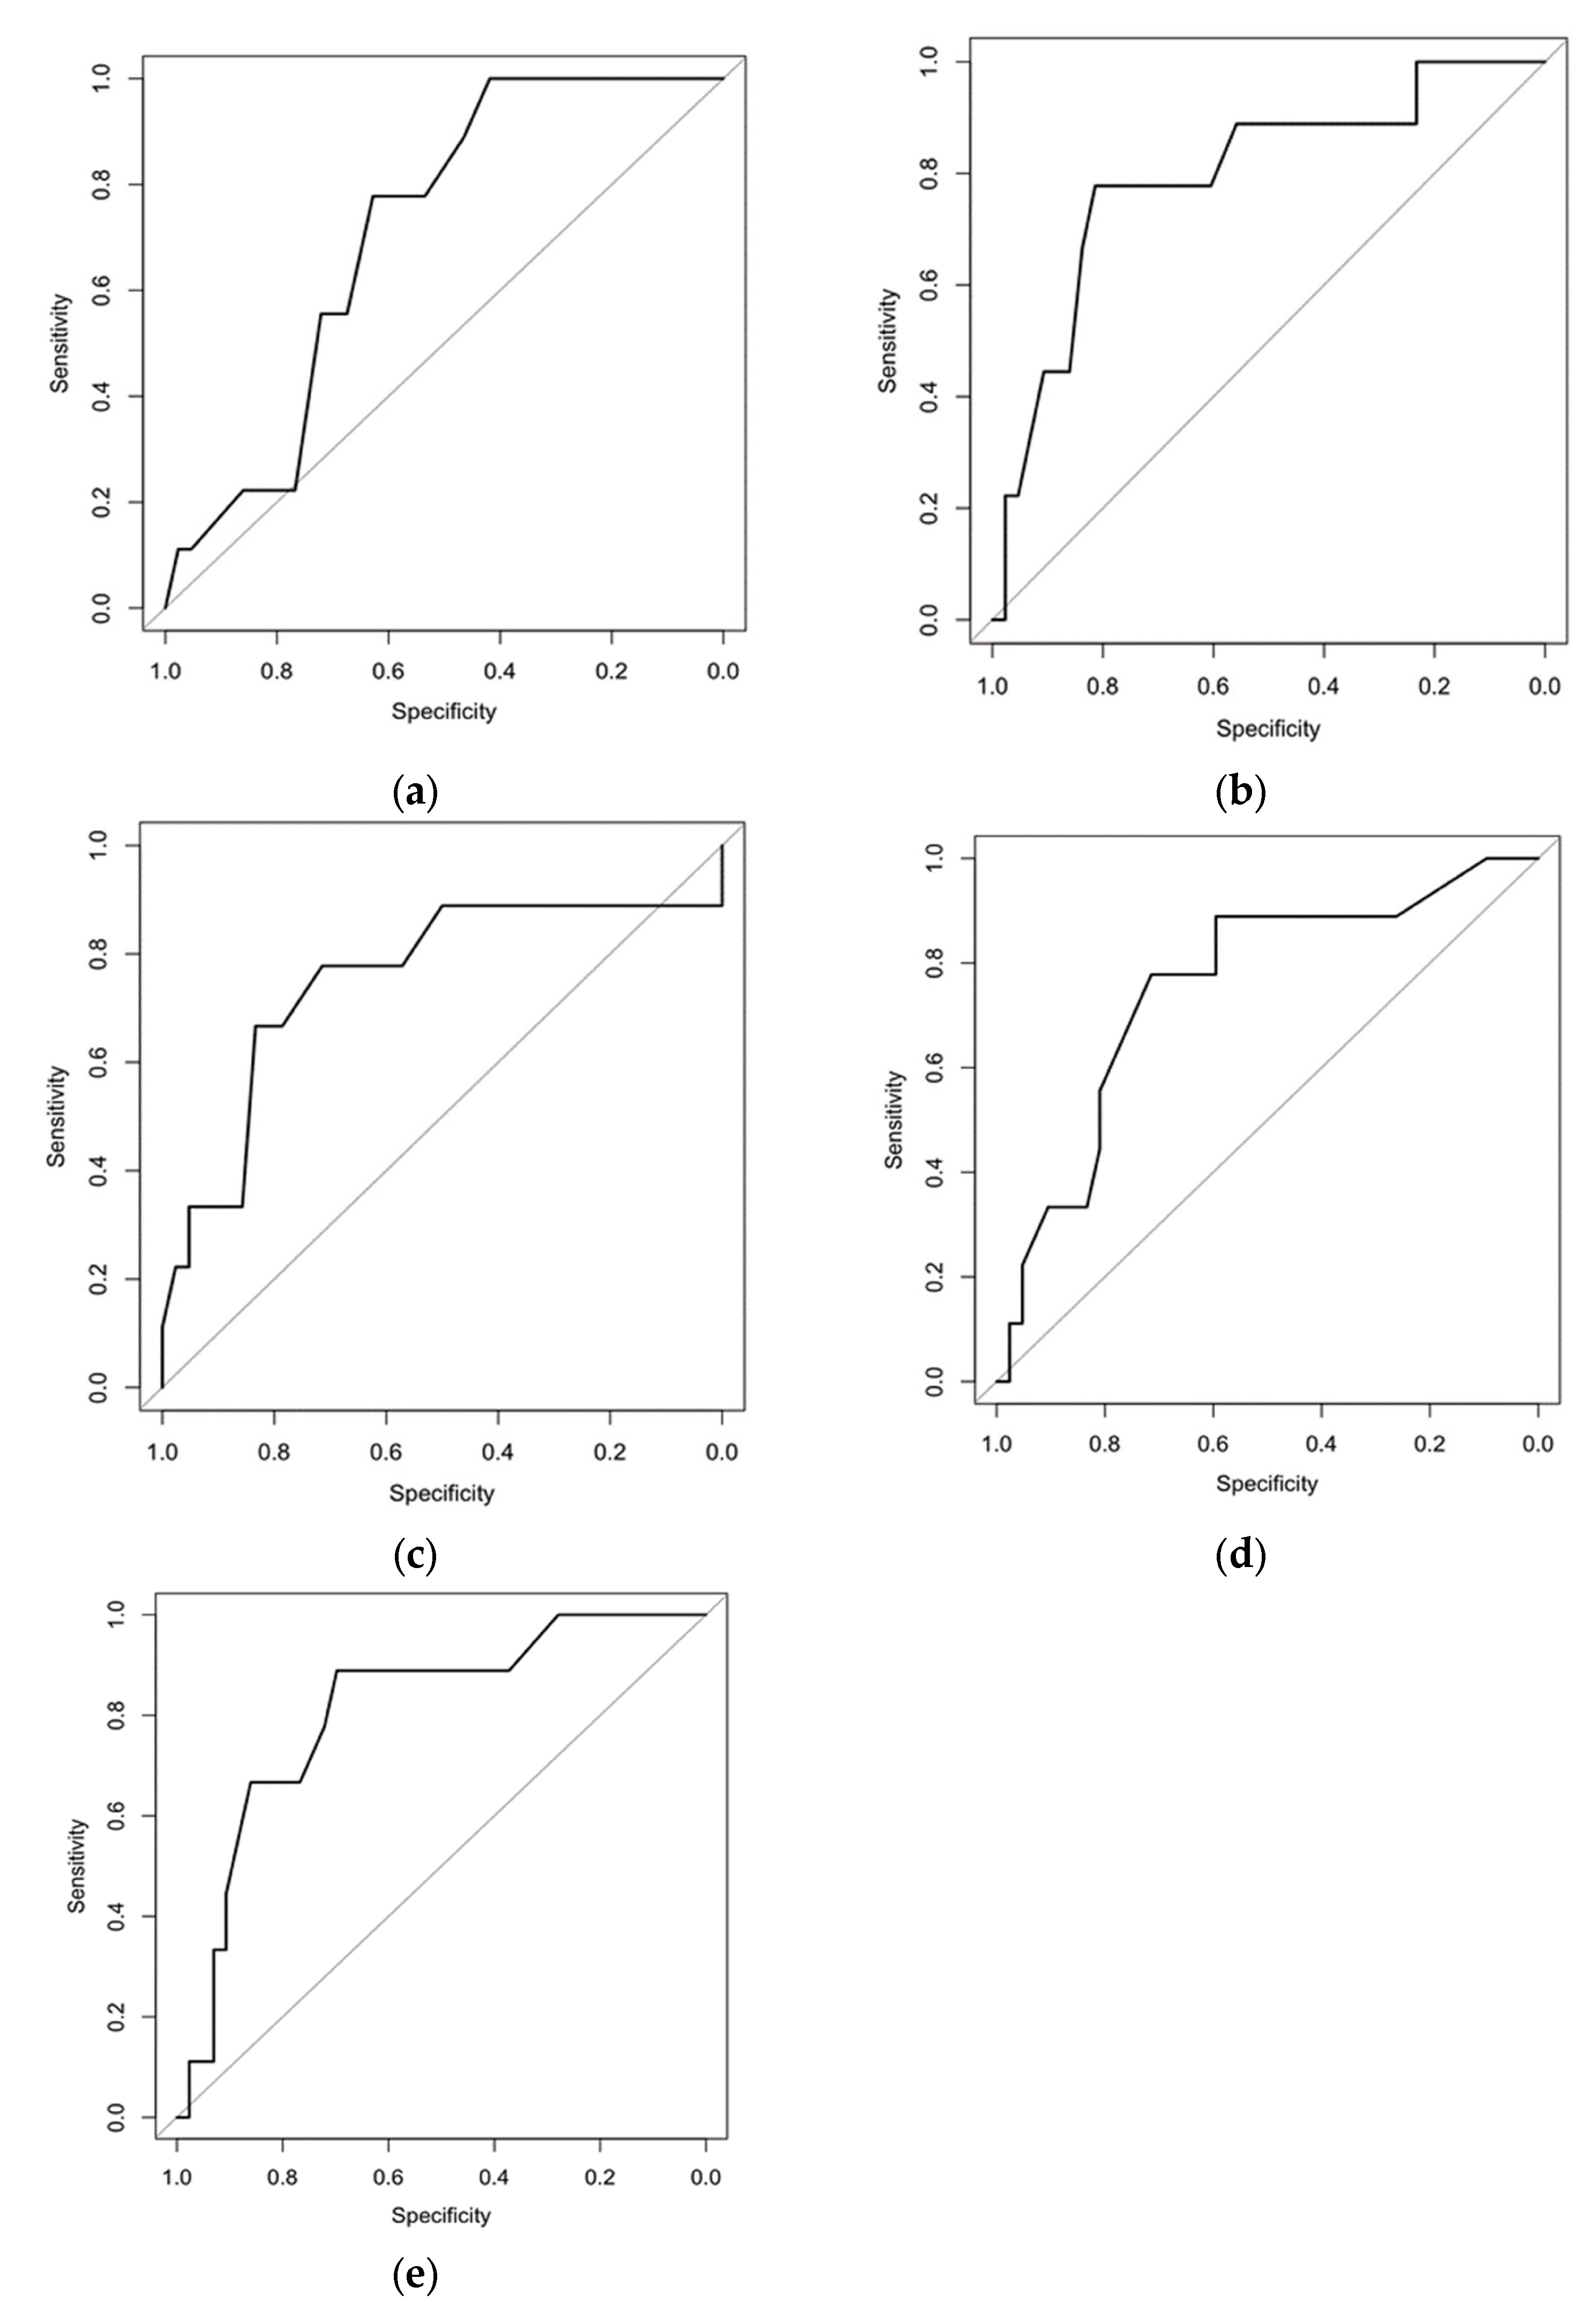

2.2. Follow-Up Testing and Modeling for Predicting the Course of Sarcoidosis

3. Results